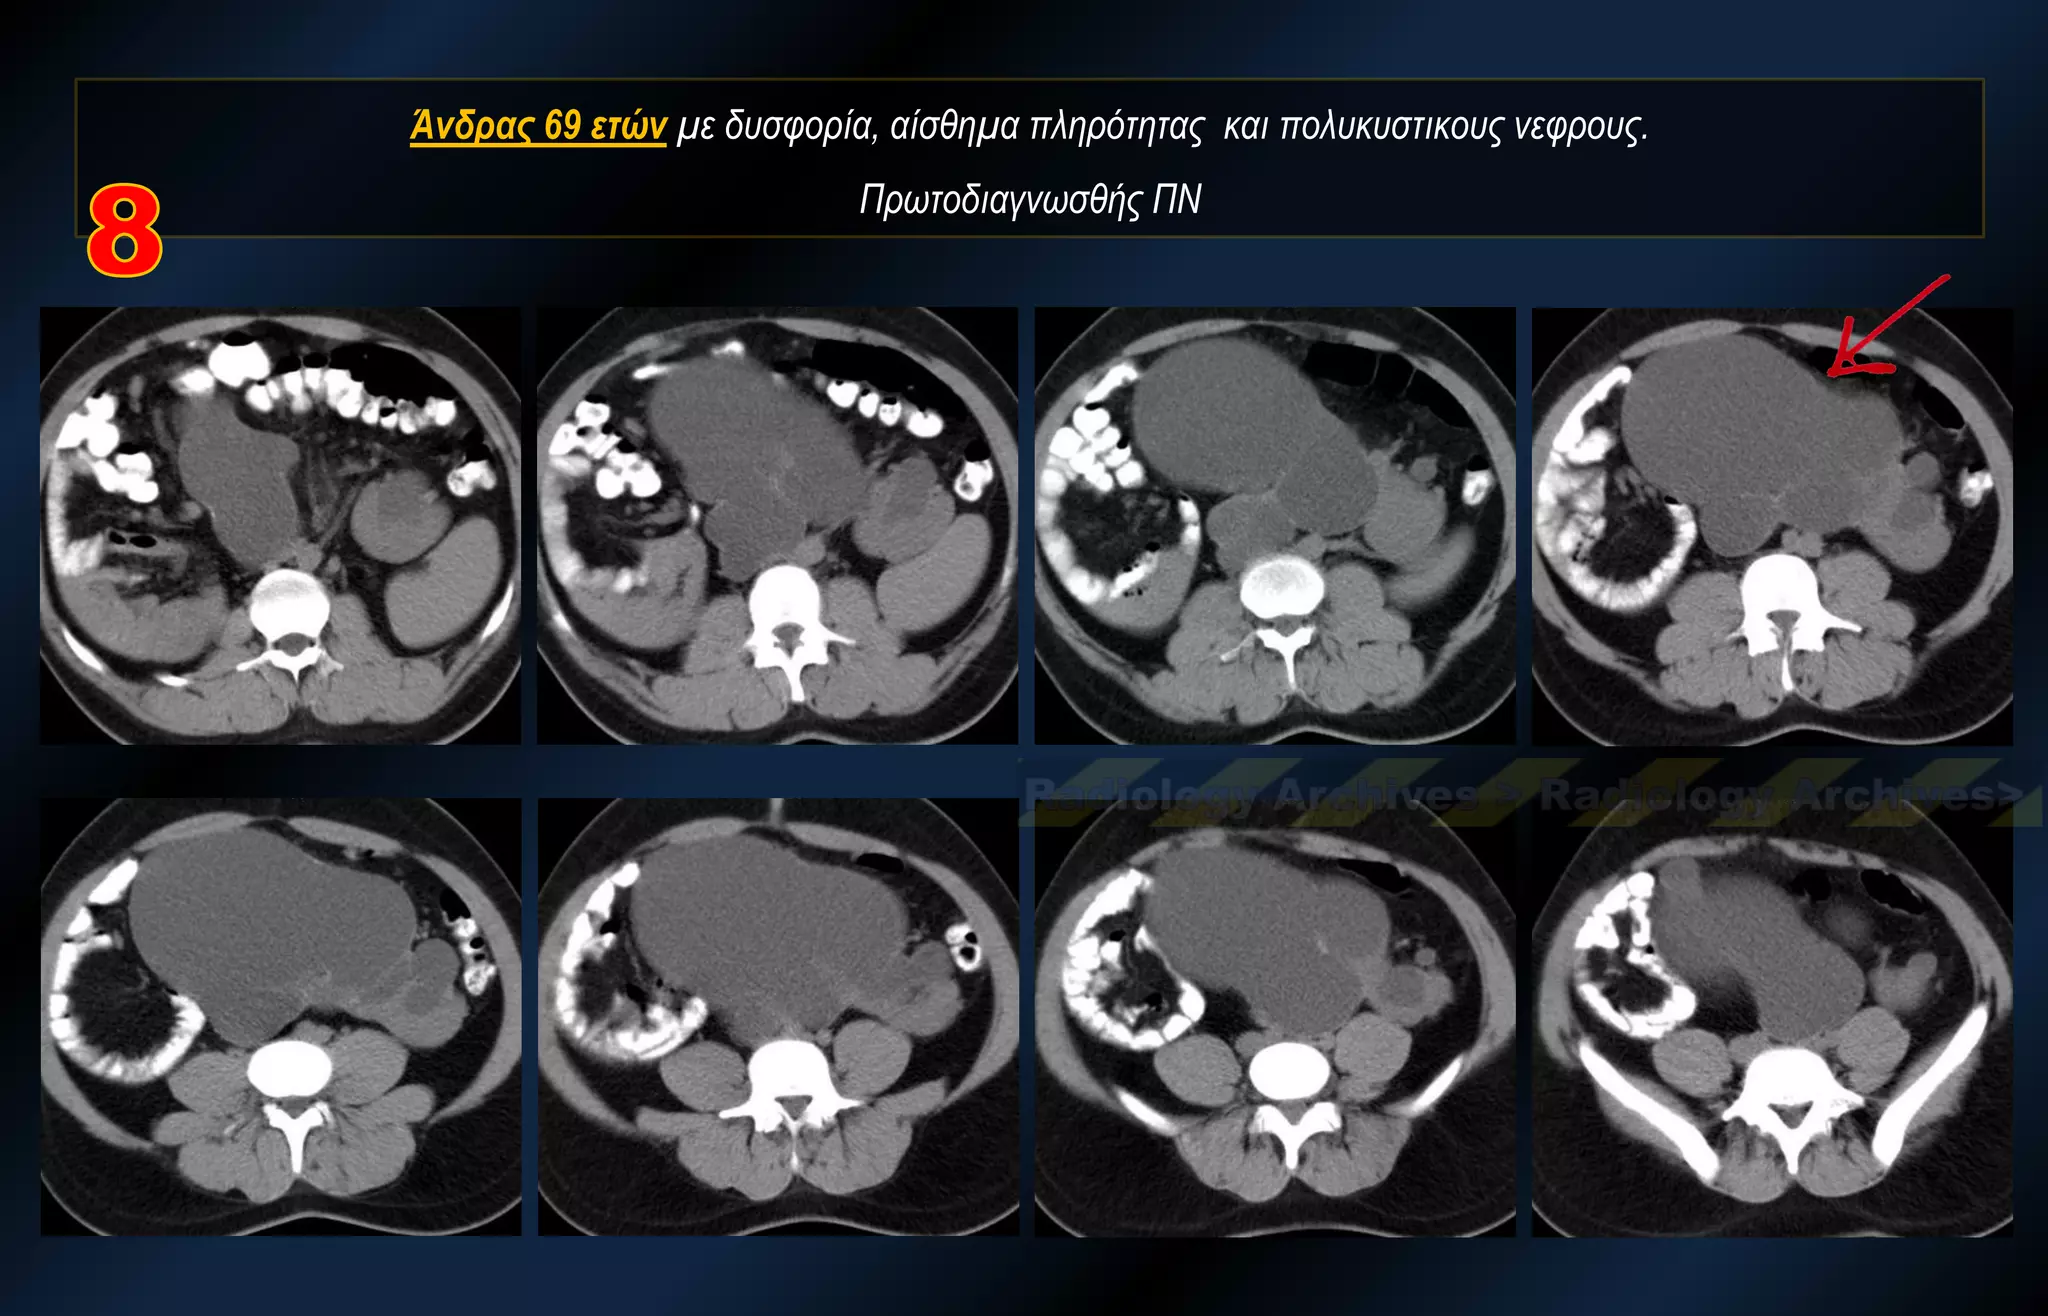

Άνδρας 69 ετών με δυσφορία, αίσθημα πληρότητας και πολυκυστικους νεφρους. Πρωτοδιαγνωσθής ΠΝ

Άνδρας 69 ετώνμε δυσφορία, αίσθημα πληρότητας και πολυκυστικους νεφρους. Πρωτοδιαγνωσθής ΠΝ